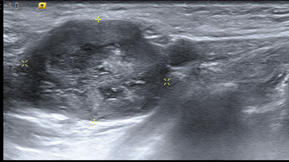

La ECO constituye el complemento ideal de la mamografía. Un nódulo sólido (fibroadenoma o cáncer) presenta la misma densidad radiológica que un nódulo líquido (quiste), por ello la ecografía permite distinguir sin problemas el contenido líquido del sólido. Sin embargo, tiene como limitación el hecho de que no es posible obtener una visión de toda la mama en una sola imagen. Pueden por tanto pasar fácilmente

desapercibidas lesiones pequeñas, La ecografía nos es útil para controlar la punta de la aguja en caso de punciones guiadas.

Mama hipoecogenica heterogénea con múltiples focos ecogénicos en relación con microcalcificaciones vistas en mamografía. lo anterior, se corresponde a un BIRADS 6, que se corresponde con un carcinoma ductal localmente avanzado con diagnóstico anatomopatológico.

DIAGNÓSTICO FINAL: CARCINOMA DUCTAL LOCALMENTE AVANZADO.